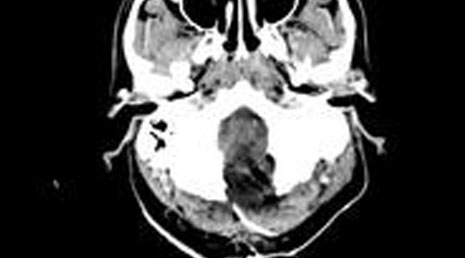

52. Subdural hematoma